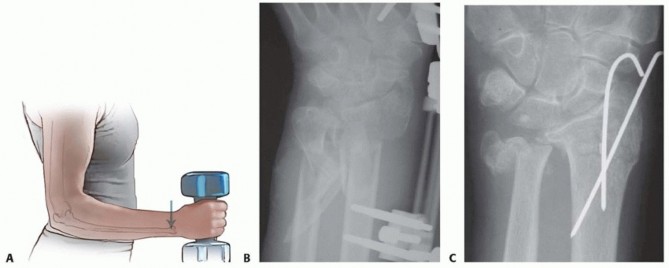

K-Wire Fixation of Distal Radius Fractures with and without External Fixation

Intramedullary and Dorsal Plate Fixation of Distal Radius Fractures